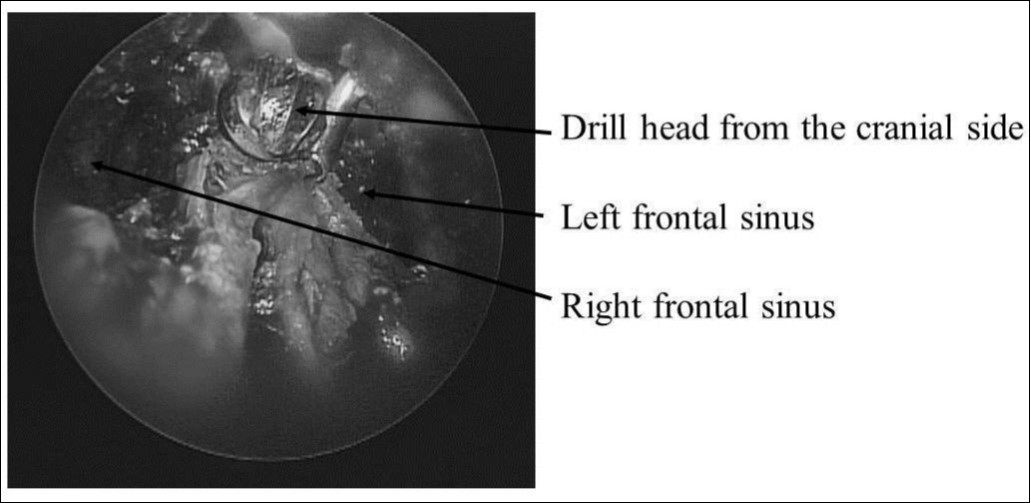

On April 28, 2007, craniotomy was performed under general anesthesia, with removal of the ceramic implant and median drainage of the frontal sinus (Figure 2). Two cysts in the left lateral frontal sinus were opened. One cyst was inflamed with thickened mucosa. The left and right frontal sinuses were opened widely, the anterosuperior nasal septum was excised, and a large drain was placed (Figure 3). A new ceramic implant was not placed because of infection and contamination. The operative time was 4 h 25 min (surgery completed at 18:30). Blood loss was 400 mL, without the need for any transfusions. During endotracheal intubation and extubation, no significant changes in blood pressure were observed, nor were any arrhythmias identified. During surgery, epinephrine gauze (1:5000) was used several times, and a total of 15 mL of epinephrine (1:20,0000) was injected intranasally. Specifically, no intraoperative manipulation or compression of the left eye was performed. Just before completion of surgery, gauze with Achromycin ointment was packed into the nasal cavity, the absence of bleeding was confirmed, and surgery was completed.

Figure 3.Frontal sinus median drainage by nasal endoscopy. Drill head from the cranial side. The left and right frontal sinuses were opened.